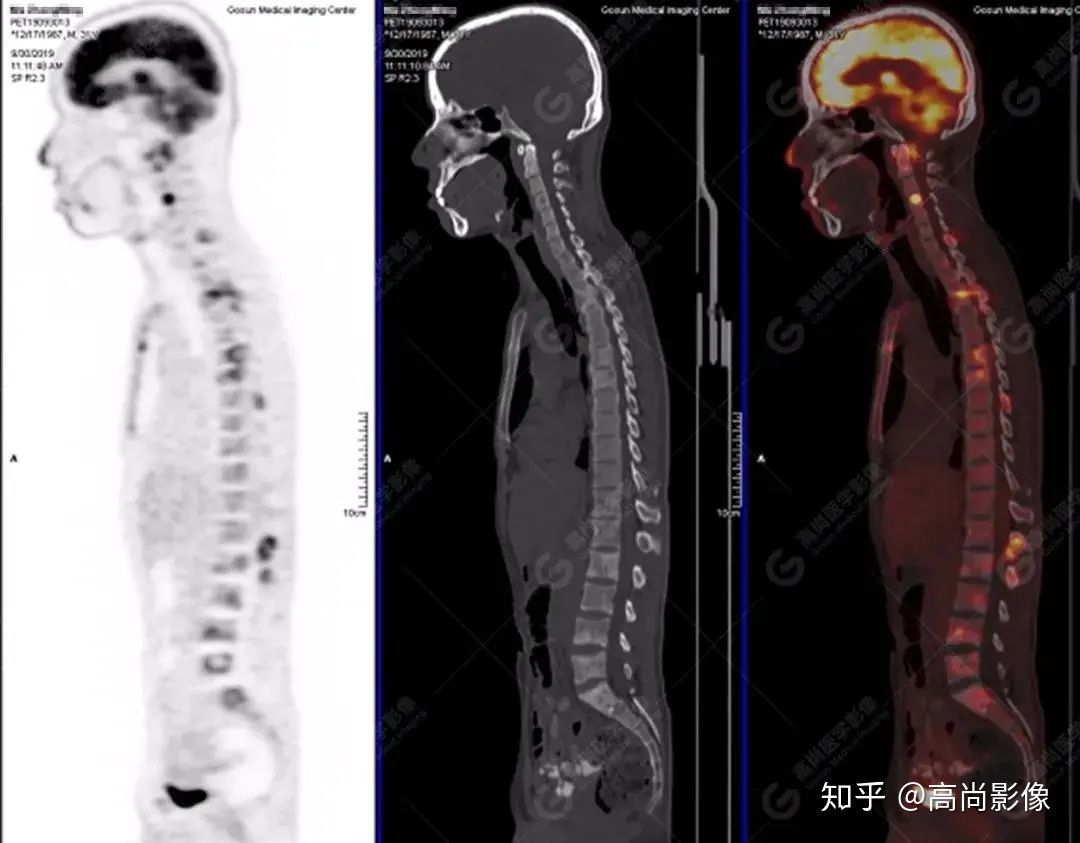

脊柱多發(fā)椎體及附件骨質(zhì)破壞,代謝不均性增高

全身多處骨質(zhì)破壞,代謝不均性增高

【PET/CT提示】雙肺、左側(cè)胸膜多發(fā)結(jié)節(jié)影,全身多處骨質(zhì)破壞,全身多發(fā)淋巴結(jié)腫大,代謝攝取不均勻性增高。

2.全身多系統(tǒng)、多形態(tài)、多發(fā)病灶(肺部、胸膜、淋巴結(jié)、骨),18F-FDG攝取不均性增高;

特征:肺部病灶簇狀分布,上葉尖段及下葉背段為著;腫大淋巴結(jié)分布不對稱,無融合、中央有壞死改變,與淋巴瘤、轉(zhuǎn)移瘤等有一定的鑒別診斷意義;